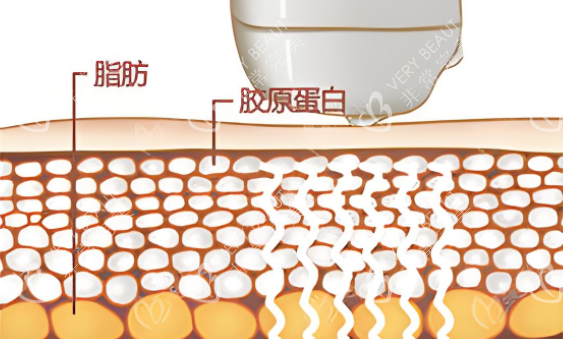

超声波碎脂:通过2.45GHz微波穿透脂肪层,使水分震荡产生60-70℃热能

双重作用:脂肪细胞分解代谢的同时,刺激胶原纤维收缩重组

探头设计:3mm浅层探头改善细纹,7mm深层探头提拉筋膜